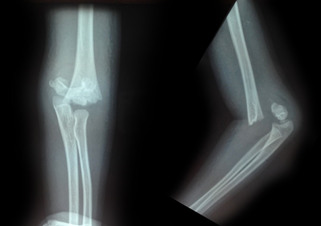

All the fractures united with no loss of carrying angle or cubitus varus deformity. According to Flynn’s grading system for elbow function, 41 patients (89.1%) achieved excellent results and one patient had poor result as shown in Table 2. Five patients (10.8%) had superficial pin site infection that went to heal with local pin site dressings only. None of them had chronic discharge after the wire removal. No complications like ulnar nerve injury, vascular injury, compartment syndrome, myositis ossificans, malunion, and non-unions were noted (Figures 1-4).

Figure 4 Follow-up X-rays – 3-month postoperative.